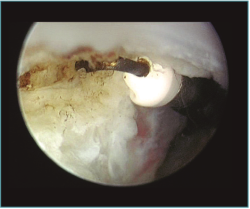

Método: hemos revisado 38 pacientes con codo rígido postraumático o degenerativo que se trataron mediante artrolisis artroscópica entre 2013 y 2016, con un seguimiento medio de 25 meses (38-15). Según la etiología de la rigidez, clasificamos a los pacientes en 2 grupos: grupo 1, los pacientes con rigidez por patología degenerativa del codo, y grupo 2, los pacientes con rigidez postraumática. Clasificamos la rigidez siguiendo la escala de Morrey y utilizamos la escala funcional Mayo Elbow Performance Index (MEPI), que evalúa el dolor, la movilidad, la estabilidad y la función del codo pre- y postoperatoriamente. Describimos los procedimientos artroscópicos realizados en cada paciente, que incluyen la sinovectomía, el desbridamiento de tejido fibroso, la capsulectomía anterior y/o posterior, la resección de osteofitos en la parte anterior y posterior del codo, la extirpación de cuerpos libres y la liberación “abierta” del nervio cubital.

Method: a review was performed on 38 patients with stiff elbow due to degenerative or post-traumatic reasons, and who were treated by arthroscopic arthrolysis between 2013 and 2016, with a mean follow-up of 25 months (38-15). Elbow stiffness was classified following the Morrey scale and the Mayo Elbow Performance Index (MEPI) functional scale was used to evaluate pain, mobility, stability and elbow function pre- and post-operatively. The arthroscopic procedures performed on each patient are described, including synovectomy, debridement of fibrous tissue, anterior and/or posterior capsulotomy, resection of osteophytes in the anterior and posterior part of the elbow, extirpation of loose bodies and open release of the ulnar nerve.